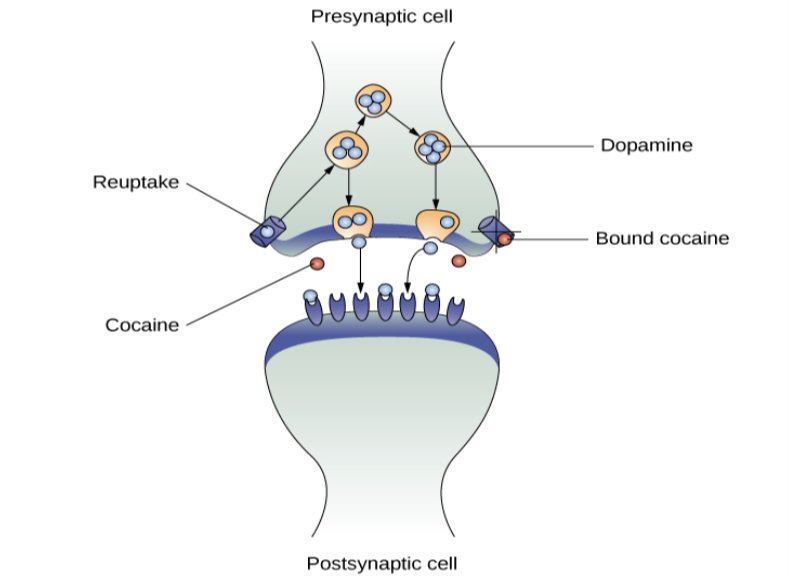

Cocaine can be taken in multiple ways. While many users snort cocaine, intravenous injection and inhalation (smoking) are also common. The freebase version of cocaine, known as crack, is a potent, smokable version of the drug. Like many other stimulants, cocaine agonizes the dopamine neurotransmitter system by blocking the reuptake of dopamine in the neuronal synapse.

Amphetamines have a mechanism of action quite similar to cocaine in that they block the reuptake of dopamine in addition to stimulating its release (Figure 4.16). While amphetamines are often abused, they are also commonly prescribed to children diagnosed with attention deficit hyperactivity disorder (ADHD). It may seem counterintuitive that stimulant medications are prescribed to treat a disorder that involves hyperactivity, but the therapeutic effect comes from increases in neurotransmitter activity within certain areas of the brain associated with impulse control. These brain areas include the prefrontal cortex and basal ganglia.